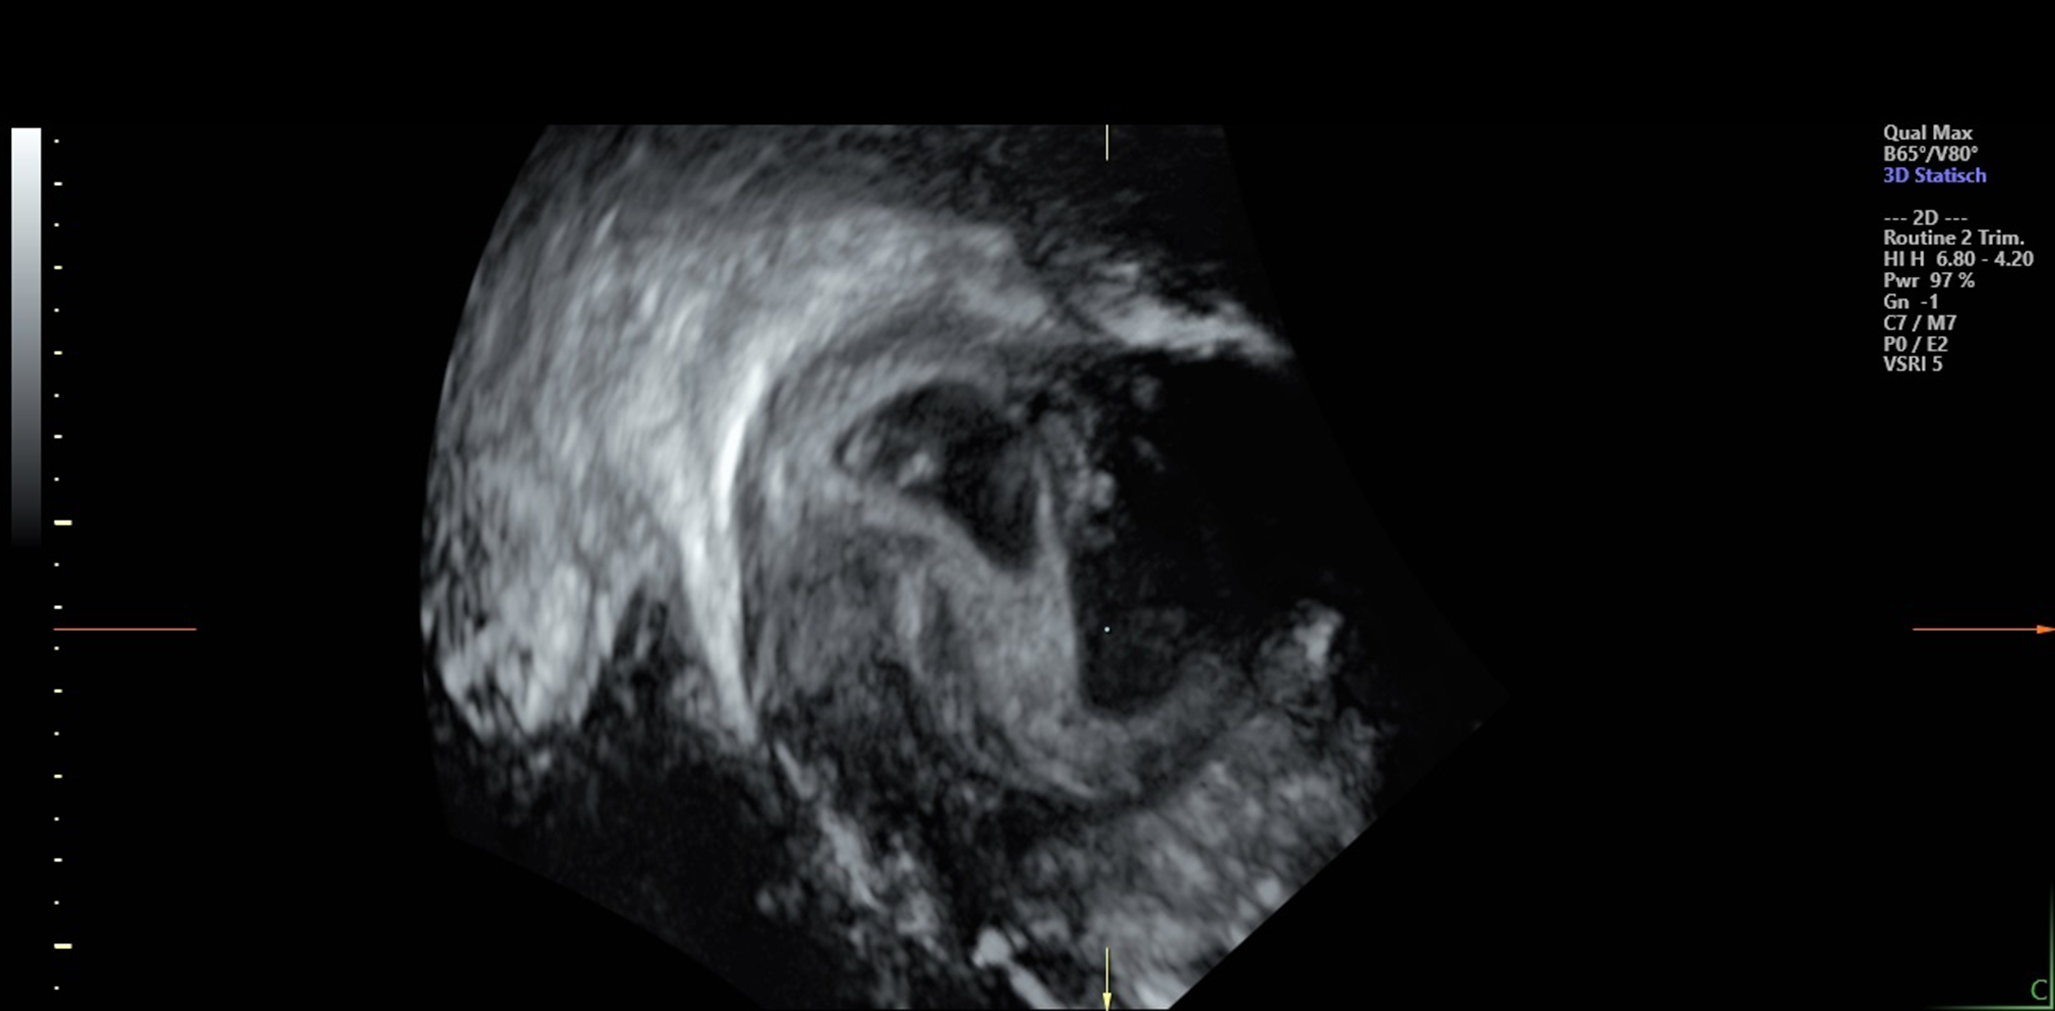

Fig. 1

Ultrasound images from the 10th week of a dichorionic diamniotic twin pregnancy, where the twins are separated by a thick layer of fused chorionic membranes. Patient permission has been granted

Knowing the different timelines and kinds of twin formation was of great importance for the presented case - a gemini pregnancy after transferring a single embryo in the ICSI cycle. For twin differentiation in DCDA, MCDA, or MCMA, diagnosis is regularly conducted by ultrasound, which is well-established in obstetric care [16, 17]. Here, ultrasonography at week ten revealed that the twins were DCDA, i.e., each fetus had its placenta and amniotic sac. According to the aforementioned criteria, this twinning type would have been expected for blastocyst cleavage within the first three days after fertilization. However, the responsible foreign clinic transfers the zygote exclusively at a late blastula stage, which – if twinning had occurred – an MCDA or MCMA pregnancy would have been expected. In addition to the clinically unexpected twin type, other factors increased uncertainty about correct embryonic implantation. For instance, information about the number of the patient’s remaining embryos was contradictory. Further, another woman should have had multiple embryos transferred on the same day of the patient’s implanting treatment. Moreover, the clinic abroad refused to provide additional requested documentation about the implantation. Therefore, the couple suspected that the planned transfer of one fertilized oocyte was a mix-up with the other clinic case, with multiple embryos to be implanted. Although the couple wished to have a child and, in principle, would have adopted twins, the doubts about whether the embryos were their biological children caused an emerging desire to terminate the pregnancy unless genetic confirmation of their parenthood was proven. While it could be contradictorily discussed to abort a child after an artificial treatment, it must be stated that the possible event of an embryonic mix-up clearly is not a free decision of either of the couples involved and such potential error should be clarified with respect to the genetic confirmation of parenthood.